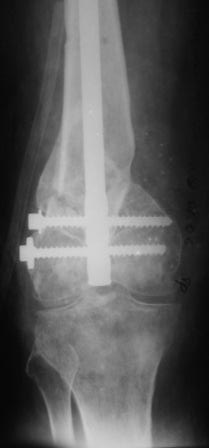

Уважаемые коллеги! Представляю на ваш суд ближйший результаты лечения.

На момент операции не было возможности запечатлеть увиденное, поэтому попытаюсь пересказать.

Первое что пришло в голову по аналогии очень похоже на асептический некроз головки бедра когда головку извлекают при эндопротезировании.Хрящ внутреннего мыщелка бедра был отслоен и изменен,сам мыщелок проминался под пальцем. От блокирования стяжкой отказались. Можно ли это расценить как асептический неркоз внутреннего мыщелка в результате первичной травмы?

Леонид Соломин писал о случае с пателлофеморальным синдесмозом(спасибо), но к сожалению сообщение пришло уже после операции.Прежде мы не встречались с подобным.Во время мобилизации после артролиза, отсечения интремедиуса попытались согнуть колено: хрящ надколенника остался на мыщелках бедра(!). В результате приняли решение удалить надколенник.

Раннее послеоперационное течение не очень спокойное- из раны было сукровичное отделяемое, но сейчас вроде идет на поправку(на фоне интенсивного лечения). В аттаче рентгенограммы.

Жду ваших комментариев!

Рентгенограмма симпатичная...